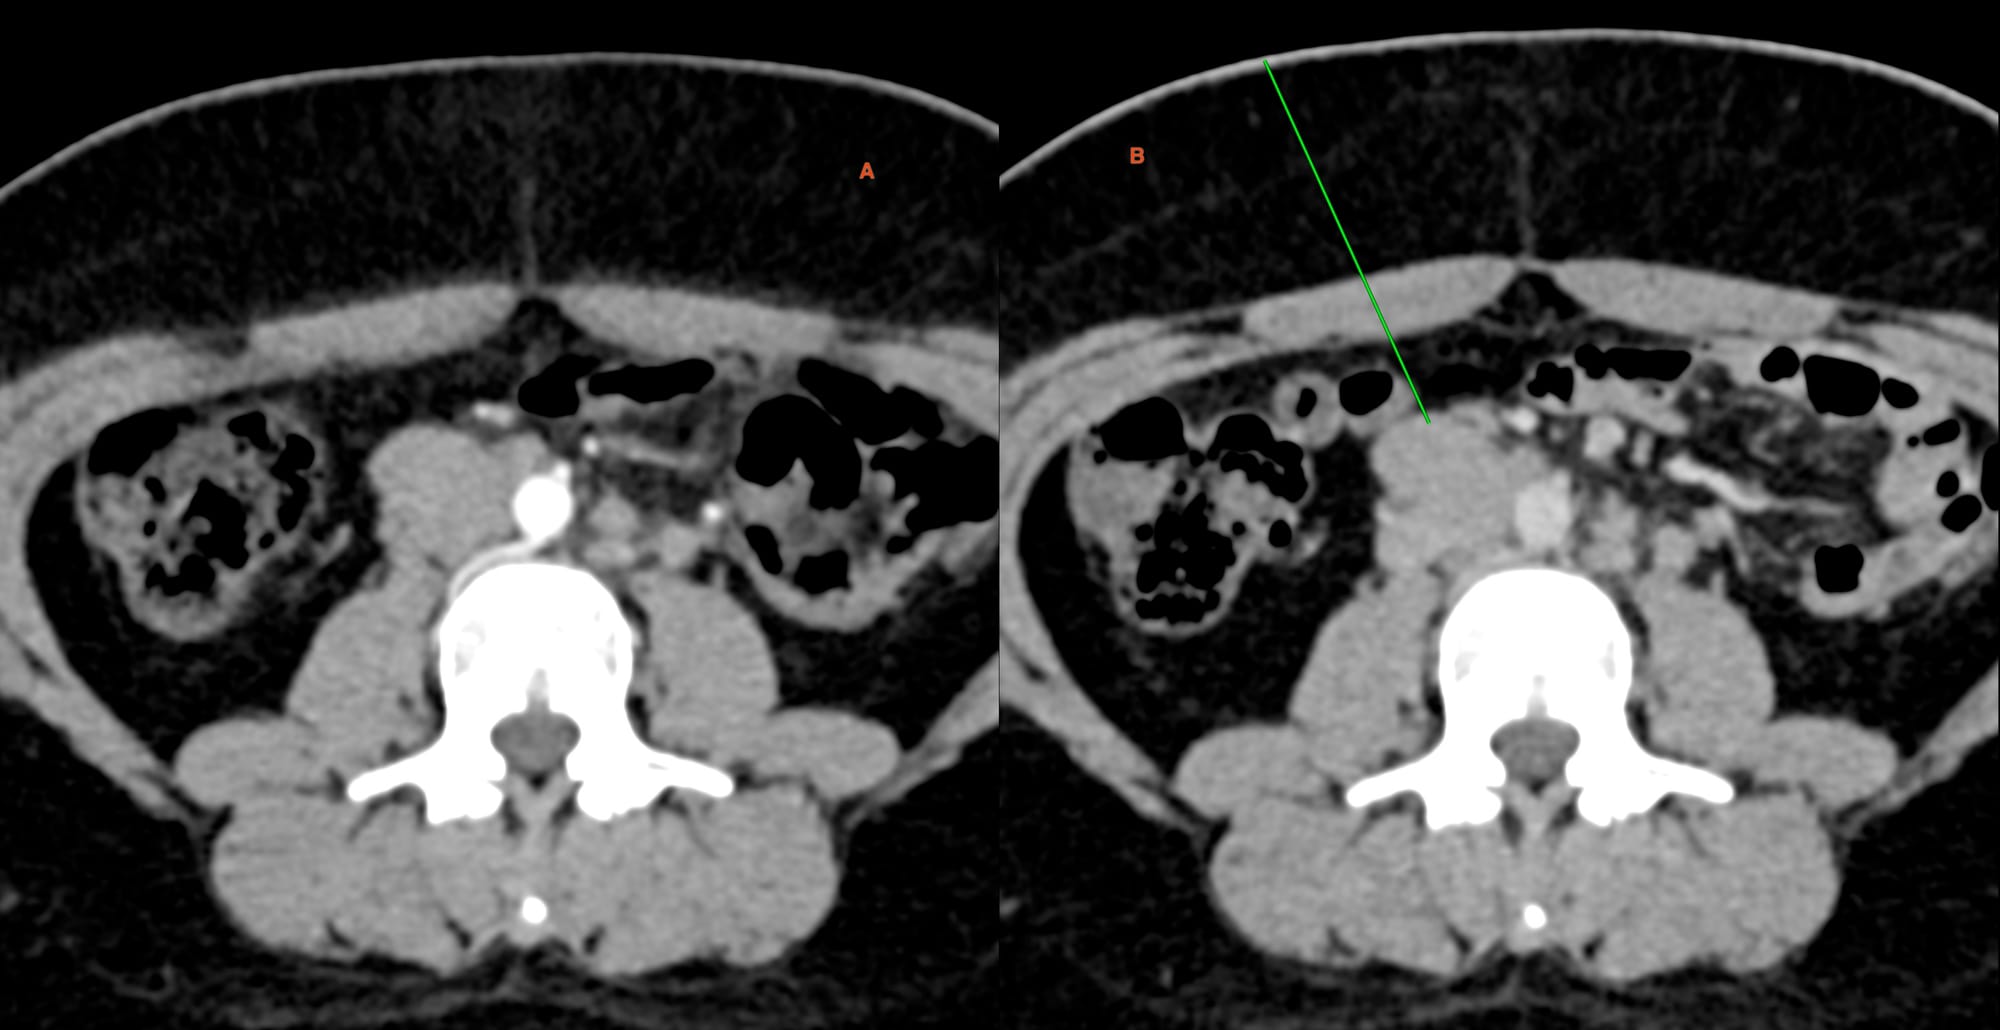

Fig. 4. Panel shows the 18G BARD, 20 mm throw gun with a straight entry into the node (A, B). After withdrawing the stylet, the canal is pulled up to the proximal edge of the node (C). I used a hub to reduce the throw to 10 mm (D) and deployed the gun.

As Fig. 5 shows, it took 9 minutes for 5 cores for histopath.

Diagnosis was metastasis from ovarian dysgerminoma.